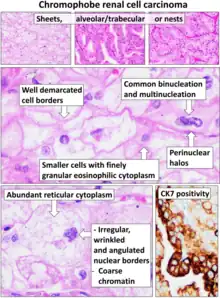

Chromophobe Renal Cell Carcinoma (ChRCC)

ChRCC consists of tumor cells with well demarcated borders and abundant pale to eosinophilic cytoplasm. |

3–5% |

The gross and microscopic appearance of renal cell carcinomas is highly variable. The renal cell carcinoma may present reddened areas where blood vessels have bled, and cysts containing watery fluids.[58] The body of the tumour shows large blood vessels that have walls composed of cancerous cells. Gross examination often shows a yellowish, multilobulated tumor in the renal cortex, which frequently contains zones of necrosis, haemorrhage and scarring. In a microscopic context, there are four major histologic subtypes of renal cell cancer: clear cell (conventional RCC, 75%), papillary (15%), chromophobic (5%), and collecting duct (2%). Sarcomatoid changes (morphology and patterns of IHC that mimic sarcoma, spindle cells) can be observed within any RCC subtype and are associated with more aggressive clinical course and worse prognosis. Under light microscopy, these tumour cells can exhibit papillae, tubules or nests, and are quite large, atypical, and polygonal.

Nuclear grade is believed to be one of the most imperative prognostic factors in patients with renal cell carcinoma.[24] However, a study by Delahunt et al. (2007) has shown that the Fuhrman grading is ideal for clear cell carcinoma but may not be appropriate for chromophobe renal cell carcinomas and that the staging of cancer (accomplished by CT scan) is a more favourable predictor of the prognosis of this disease.[63] In relation to renal cancer staging, the Heidelberg classification system of renal tumours was introduced in 1976 as a means of more completely correlating the histopathological features with the identified genetic defects.[64]